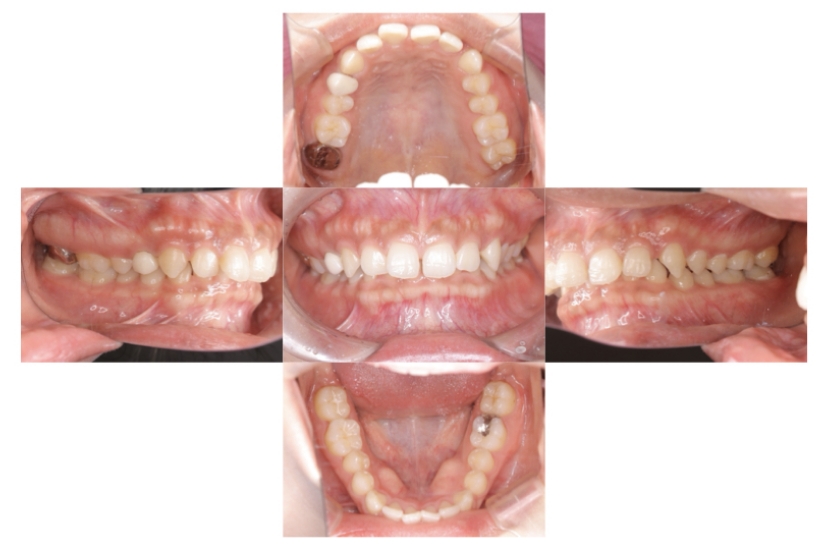

症例1

上顎前突、叢生

抜歯

ブラケット矯正

上下顎叢生、上顎前突(出っ歯、上下の前歯のガタガタ)のケースです。

装置はラビアル(上下表側)で、上顎の小臼歯を2本抜歯を行っています。抜歯したスペースを使って、上の前歯の後方移動と叢生(ガタガタ)と出っ歯の改善を行っています。下は歯と歯の間にIPR(隣接面削合)を行い、スペースを確保し、叢生の改善を行っています。

主訴 前歯のガタガタと出っ歯が気になる。

年齢・性別 47歳 女性

お住まいの地域 神奈川県川崎市

治療方針 抜歯スペースおよびIPRを利用して上前歯の叢生(ガタガタ)の改善

抜歯部位 上顎左右第一小臼歯

使用装置 ラビアル(上下表側)、顎間ゴム

治療期間 2年0か月

治療回数 15回

リテーナー クリアリテーナー

BEFORE

AFTER